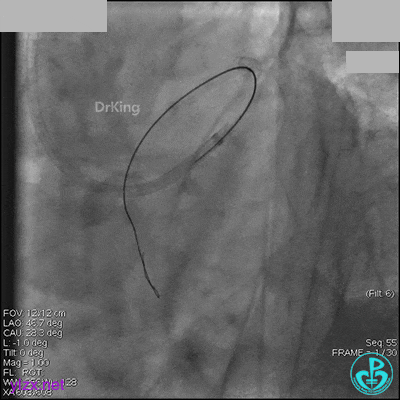

冠脉造影

入院次日冠脉造影显示粗大左主干末端中度狭窄,前降支开口严重狭窄,回旋支与前降支角度大,弥漫性长病变,严重狭窄,粗大右冠脉近中段弥漫性中重度狭窄。由于病变复杂,造影结束后先下台,择期再行介入治疗。

AL 1.0指引导管到位,简单短时尝试导丝不能顺利通过前降支或回旋支病变。改变策略处理右冠脉病变,计划植入2枚支架。AL指引导管到位,Sion blue导丝到达右冠脉远端。导丝通过后1.5mm及2.5mm球囊14~16atm充分扩张中段病变。

右冠脉中段充分扩张后欲植入3.5×38mm支架时,支架难以通过中远段扭曲处,且指引导管、导丝弹出飞扬。反复尝试导丝重新到达右冠脉远端时通过不顺利,局部造影剂滞留,远端血流接近3级。